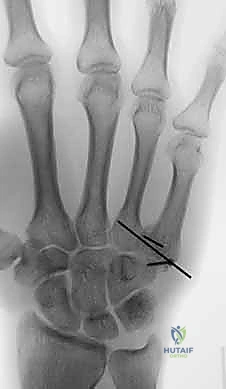

دليلك الشامل لكسور وخلع مفصل قاعدة الإصبع الكربوميتاكاربال: التشخيص والعلاج مع الأستاذ الدكتور محمد هطيف

تعرف على كسور وخلع مفصل قاعدة الإصبع الكربوميتاكاربال. دليل شامل للتشخيص والعلاج الجراحي وغير الجراحي، مع خبرة الأستاذ الدكتور محمد هطيف في…